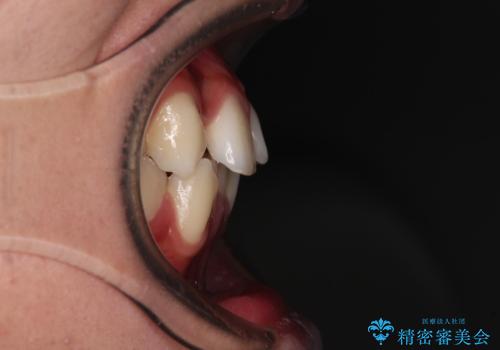

- 八重歯と口元の閉じにくさを気にして来院された患者様です。

非抜歯矯正で歯列を整えると、治療後に口元が今よりも突出する可能性が高かったため、上下左右の第一小臼歯4本を抜歯し、ワイヤー装置にて矯正治療を行うこととしました。